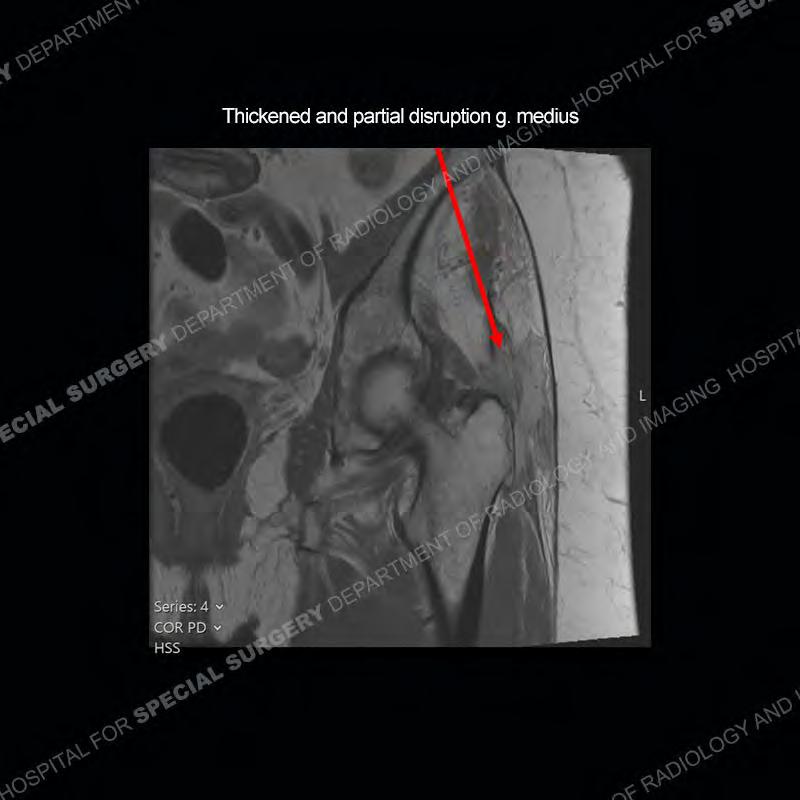

The radiograph is not particularly contributory in this case. The MRI demonstrates markedly abnormal architecture of the gluteus minimus and anterolateral band of the gluteus medius. Portions of the tendons are high signal, portions are highly attenuated, and portions are disrupted. A large, complex fluid collection is present in the adjacent soft tissue.

Diagnosis: Gluteal Tendinosis and Disruption with Complex Trochanteric Bursal Collection

Not as much of a diagnostic dilemma as many of the other cases shown but just a nice example of the pathology seen of the gluteal tendons and a cause of trochanteric pain. Although, frequently thought of in isolation, trochanteric bursitis or bursal thickening is much more commonly a reactive change to underlying pathology of the subjacent gluteal tendons. The gluteus medius is divided into a posterior band and an anterolateral band. Tendinosis and partial tearing very commonly will involve the gluteus minimus and especially the more posterior fibers and then propagate into the anterior lateral band of the gluteus medius. Involvement of the posterior band of the medius is much less common and engenders a marked degree of functional impairment.